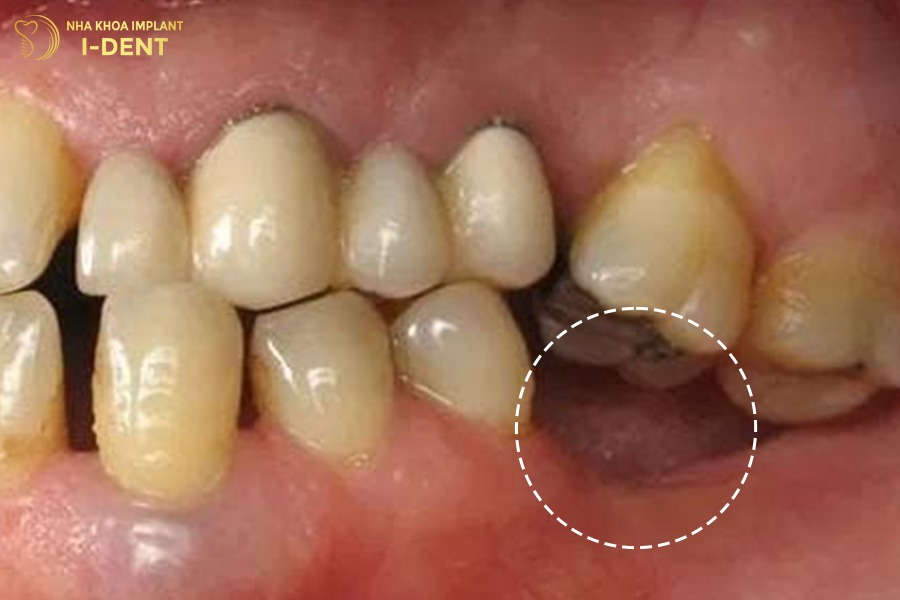

3.5. Tiêu xương hàm

Sau khi mất răng số 6 thì vùng xương hàm tại vị trí đó không còn chịu tác động của lực nhai từ chân răng. Theo thời gian, xương ổ răng sẽ dần bị tiêu đi do không còn kích thích duy trì mật độ xương, kéo theo tình trạng tụt nướu. Tiêu xương hàm càng nhiều, khu vực đó càng lõm xuống gây khó khăn khi trồng răng sau này.

Sau khi mất răng số 6 thì xương hàm tại vị trí đó tiêu biến dần.